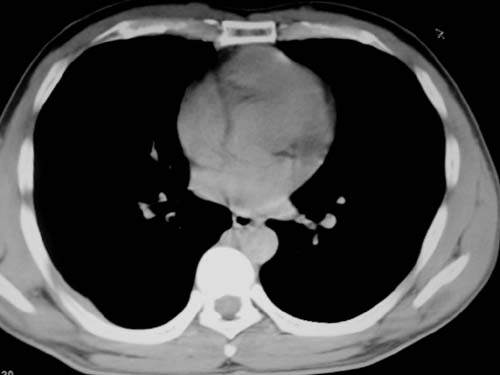

标题: CT19540: 31岁。自述结核性胸水治疗两个月后,在外院拍x线发 [打印本页]

标题: CT19540: 31岁。自述结核性胸水治疗两个月后,在外院拍x线发

右侧胸壁结节状软组织影伴相应肺叶内受侵,伴右侧胸腔积液。考虑:结核性可能大。

支持 右侧胸壁结节状软组织影伴相应肺叶内受侵,伴右侧胸腔积液。考虑:结核性可能大。

1、炎性病变,结核可能;2、右侧少量胸膜积液。

右侧胸壁结节状软组织影伴相应肺叶内受侵,伴右侧胸腔积液,结合临床,首先考虑结核。

考虑结核性胸膜炎,胸膜肥厚,不除外胸膜间皮瘤可能,建议复查。

1)考虑右侧结核性胸膜结节。2)右侧胸膜增厚+包裹性胸腔积液。

结核性脓胸、肺内结核?